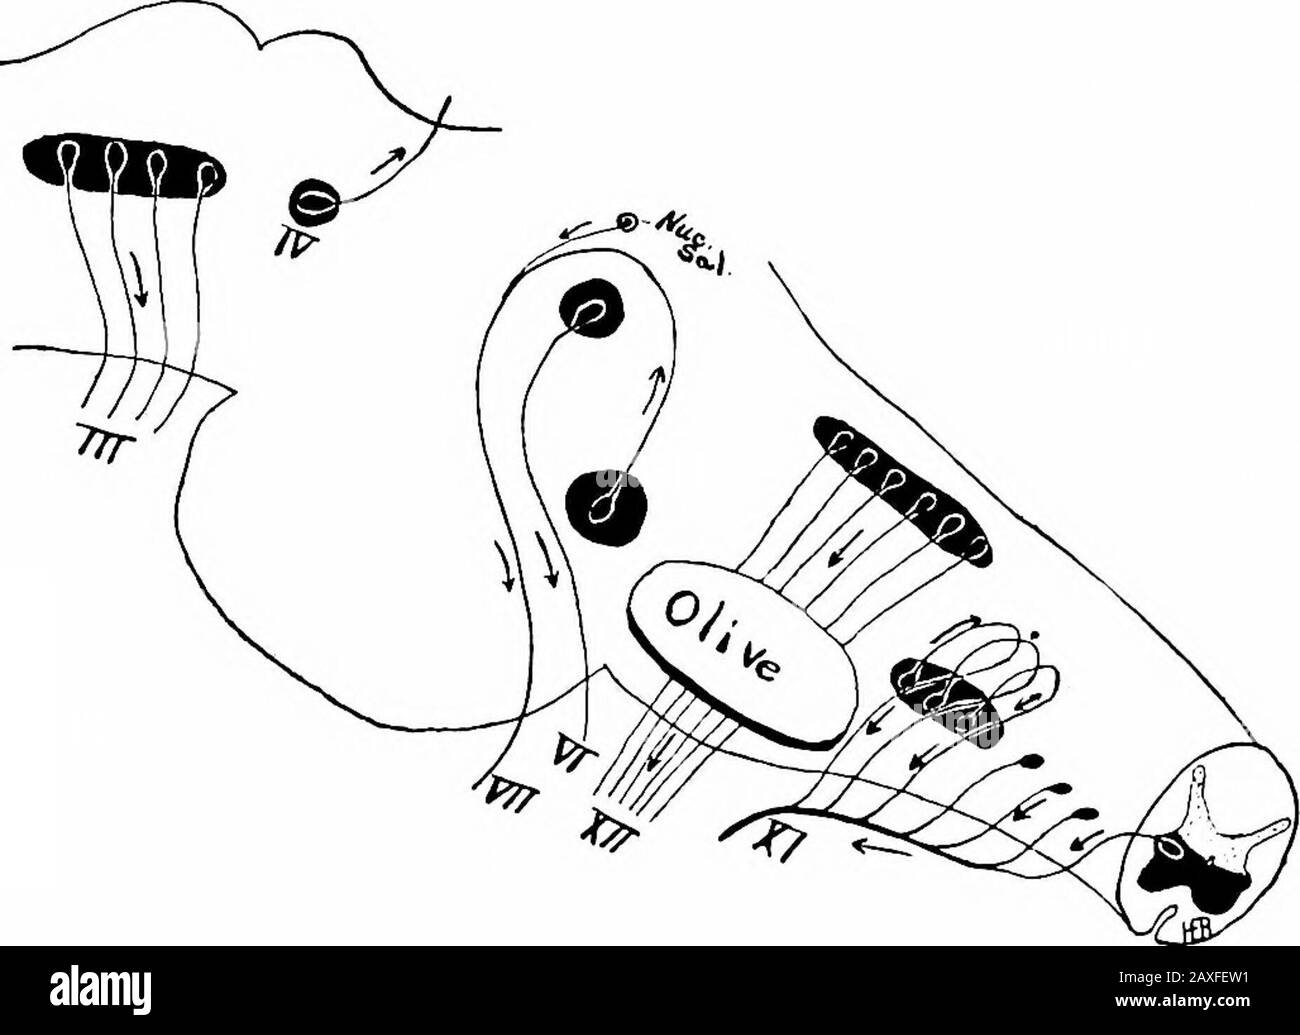

RM2AXFEW1–Ein Handbuch der Anatomie. ide. Itrests auf dem mittleren Längsfasciculus und liegt nahe an der Mittellinie. Die aus diesen Zellen entstehenden Axone gehen nach unten (cau- DER OCULOMOTOR-NERV 447 dally) und seitlich entlang des Randes des Aquäduktgraues, dem sie bis zur Mittellinie folgen; hier decussieren die Nerven am oberen Rand des übergeordneten medullären Velums und treten an der medialen Grenzlinie der Brachia contiva auf. Sie sind die kleinsten der Großhirnnerven. Diese Kerne erhalten Fasern aus dem motorischen Bereich der gegenüberliegenden Gehirnrinde durch die Pyramide. Fasern des medianlongitudinalen Fasciculus a

RM2AWH2Y3–Die Anatomie des Nervensystems, vom Standpunkt der Entwicklung und Funktion. Die Fasern des Nervus facialis Bendum den Zellkern der Entführten. Der Locus 121, DER AUS pigmentednerven Nervenzellen besteht, erstreckt sich von der Fovea Superior bis zur Thecerebral Aquädukt ist eine flache, meist blassblaue Nut, darunter liegt die substantia ferruginea. Beginnend mit dem zerebralen Aquädukt und durch das superiorale und das inferiore Fovea? Ist eine sehr wichtige Nut, der Sulcus limitans, der die Trennlinie zwischen den von t abgeleiteten Teilen wieder aufsaugt